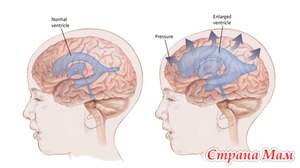

Итак, мы вами продолжаем обсуждение гидроцефалии, поговорим о третьей, само тяжелой степени дисциркуляторной энцефалопатии, типичной для проявлений гидроцефалии. При этом виде энцефалопатии проявления предыдущих стадий усугубляются сильнее. Может наступать развитие слабоумия (деменции), происходит снижение критики, в том числе и самокритики, что не дает адекватно оценивать свое и чужое поведение. При этой стадии энцефалопатии больные практически полностью утрачивают способности к мыслительным процессам. Читать далее»